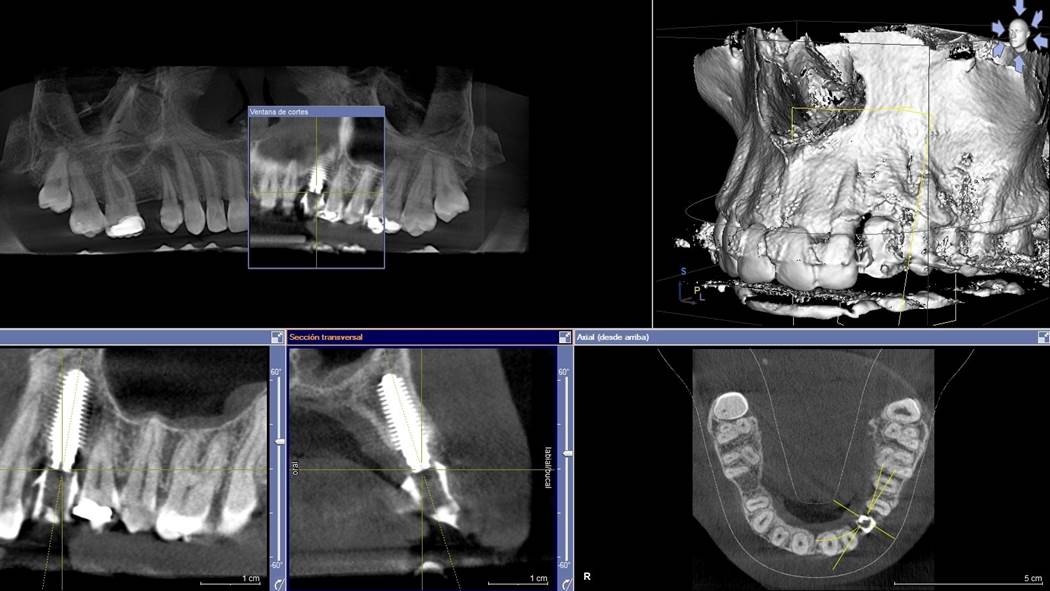

Clinical case: Digital Data Save concept in upper jaw premolar area

- Courtesy of Dr. Lysov Alexander Dmitrievich & Dr. Sofronov Matvey Vitalievich, Russia -

AnyRidge, R2GATE, R2GATE guide, ISQ value, initial stability, immediate loading, KnifeThread, maxillary posterior, #14, Digital, Dr. Lysov Alexander Dmitrievich, Dr. Sofronov Matvey Vitalievich, zirconia abutment, CAD/CAM crown

AnyRidge implant system, R2GATE, Digital prosthesis

“AnyRidge & R2GATE show stable results

after immediate extraction, immediate implant placement, & immediate loading,

even with low bone density.”